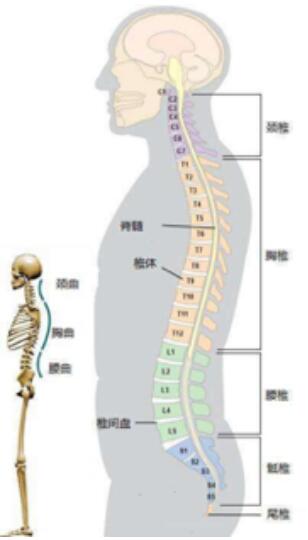

颈椎、腰椎间盘突出症患者临床肢体形态上下左右失衡、伛偻,脊柱两侧的筋肌陇壅、僵实,水肿、失衡,就说明了肌肉出现问题?有的颈椎病人难以回头,左右旋转疼痛受限,胳膊屈伸抬举困难,大家说韧带是不是也有问题了呢?还有些患者诊治时,触及筋脉、穴位时不是疼痛、酸麻、木胀感输导散溢至四肢未稍、就是涌上头面,这是不是表明气血循环、神经也有郁闭问题?所以说颈椎,腰椎间盘突出症不能说只是骨头,椎间盘的问题。而是气血、筋肉、韧带、神经、筋膜,循环、骨柱、椎间盘、津液同时都出了问题。

我们通过现代医学X光片、Ct、磁共振影像显示,病位诊断看到的只是椎骨、生理曲度、椎骨间盘结构问题。

但患者临床实际上表现呢?颈椎、腰椎间盘突出症是一个综合性的整体问题,椎骨、椎间盘只是其中的一部分而已,为什么颈椎病、腰椎病患者的肢体、关节、筋肌等部位会发生疼痛、酸麻、木胀甚至于肌肉萎缩、行为能力受限问题呢?其实就是我们中医正骨所讲的"筋出槽、骨错缝"气血瘀滞”通则不痛、痛则不通”之证。

颈椎、腰椎间盘突出症是人们在长期的工作、生活中久坐不愿活动及对筋肉劳损、挫伤的举止、习性产生的伤痛感觉无所谓,没有放在心上,殊不知,受损筋肉会能用极强的记忆力,把所受伤害储存积累下来,把其不堪重辱变成强烈的秋后算帐来报复伤其者。筋肉在长年累月的受伤害、性能退行下,影响气血运行,失却气血、津液的荣润,变得硬化、粘连、挛缩、钙化、失去韧性,失却平衡,不能够很好地保护骨柱,关节,再加上不正确的姿势或在外力作用下,出现筋挛缩、筋强、筋急、筋出槽、骨错缝、椎间盘突出、骨小关节紊乱、椎体侧弯或变直,生理结构、力线功能变异现象。筋肉、经络、血管、津液通道、骨柱、关节,扭曲、变形、相互挤压、相互绞缠、相互影响⋯⋯恶性循环状况,造成的西医医学名一一椎间盘突出临床诸痛。

我在上面讲过了,椎间盘突出症是"筋出槽、不能固骨、骨错缝、形态失衡"造成的症疾,不是大家的骨头突出,是支撑我们上肢"脊梁骨"两节椎骨之间形同圆盘状的夹层组织,西医医学名一一椎间盘突出了,椎间盘如同承重墙两块砖间的水泥沙灰夹层,其外围是坚硬性的纤维环,包裹着含水量极高、富有弹性的"果冻”状组织,西医医学名一一䯝核而组成。椎间盘环裹的纤维环在受退行、外力等因素的影响作用下出现凸隆、破裂,髓核顺势从损伤处凸隆、结构呈膨出状态;从破裂处挤溢出来,生理结构呈出壳突出状态。就如同自行车外胎出现破损、内胎露出来样的形态。